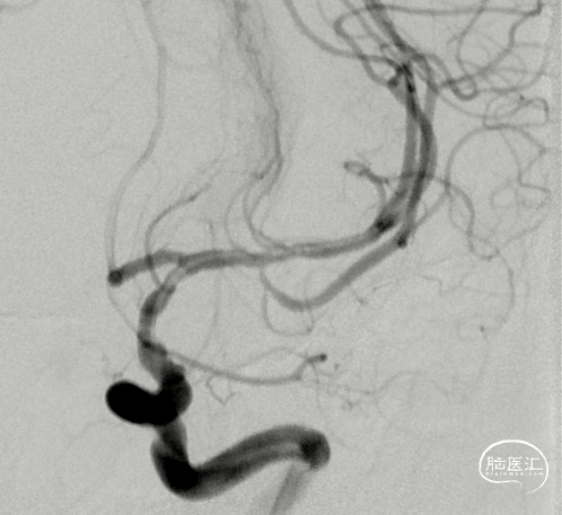

完善DSA造影提示:左侧大脑中动脉M1段末端至M2段上干近端长段重度狭窄。

造影见狭窄成形良好,远端血流改善。